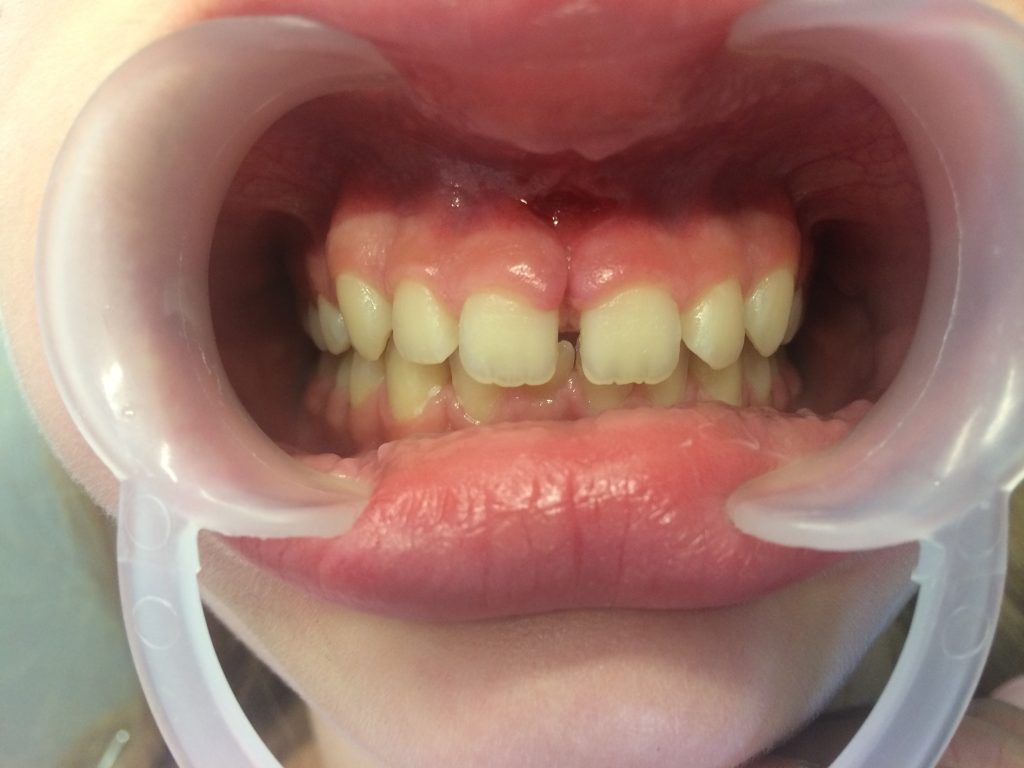

- Jedenastoletnia pacjentka została skierowana do gabinetu stomatologicznego autorów przez lekarza ortodontę w celu usunięcia przerostu wędzidełka wargi górnej przed leczeniem ortodontycznym.

Streszczenie: Metodą z wyboru w leczeniu patologicznego przerostu wędzidełka wargi górnej jest jego chirurgiczne usunięcie, które można wykonać, stosując tradycyjne narzędzia chirurgiczne (skalpel), oraz termicznie z użyciem kautera lub lasera diodowego. Frenulektomia połączona z leczeniem ortodontycznym daje bardziej stabilne wyniki niż samo leczenie ortodontyczne. Przy właściwym połączeniu obu tych metod włókna przezprzegrodowe można przekształcić w elastyczną sieć, która hamuje przemieszczenie zębów i stabilizuje ich pozycję.

Summary: The method of choice in the treatment of the pathological hypertrophy of the upper lip is its surgical removal, which can be performed using traditional scalpel surgery and thermotherapy with a kauter or diode laser. Frenulectomy combined with orthodontic treatment gives more stable results than orthodontic treatment alone. With the proper combination of these two methods, the transverse fibres can be transformed into a flexible network that inhibits the displacement of teeth and stabilizes their position.